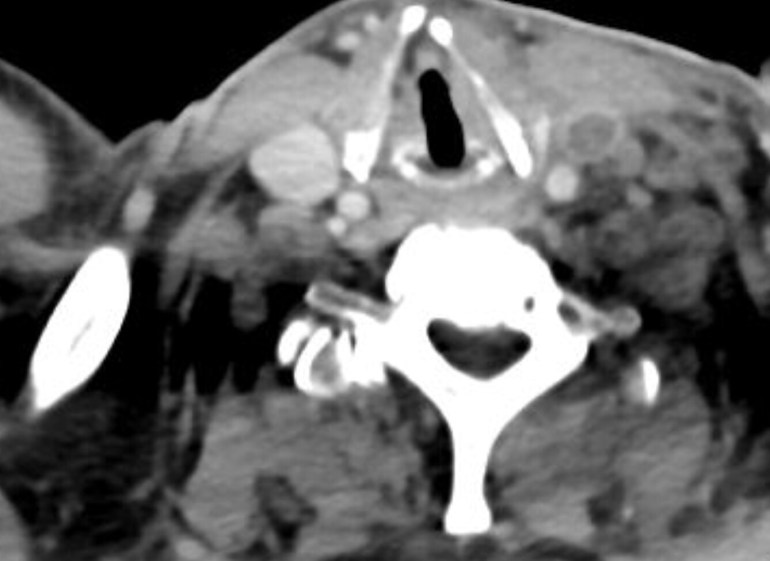

Investigations showed neutrophilic leukocytosis (WBC of 24K), cholestatic jaundice, as well as a high CRP of 217 mg/L CT of the abdomen was normal, but the following was seen at the neck and thoracic inlet.

The CT image showed thrombosis of the left internal jugular vein. Given the history of sore throat, fever with chills, as well as the findings of left neck tenderness and jaundice, the diagnosis is Lemierre’s syndrome, named after the French professor of bacteriology who described the clinical syndrome in a seminal Lancet paper in 1936. The most common cause of this disease is Fusobacterium necrophorum, although multiple other organisms can also cause internal jugular vein thrombophlebitis.